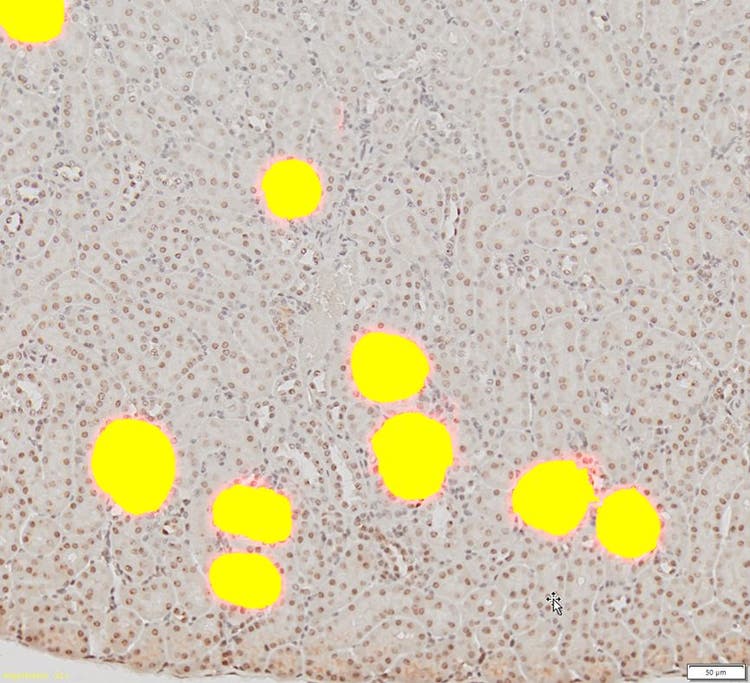

Das berechnete DNN wird auf die restlichen Nierenbilder angewendet, um die Glomeruli automatisch zu erkennen und zu segmentieren.

Schließlich wird das berechnete DNN auf die restlichen Nierenbilder angewendet, um die Glomeruli automatisch zu erkennen und zu segmentieren.

3. Die erkannten Glomeruli können segmentiert und zur weiteren Zähl- und Messanalyse des Ausgangsbildes verwendet werden.

Die erkannten Glomeruli

Das TruAI Modul ermöglichte eine einfache Erkennung und Segmentierung von Glomeruli in komplexen Bildern mit wesentlich höherer Zuverlässigkeit und Genauigkeit als andere bestehende automatische Methoden. Basierend auf diesen Segmentierungsergebnissen können zudem weitere Analysen, z. B. Zählungen und Messungen, durchgeführt werden.